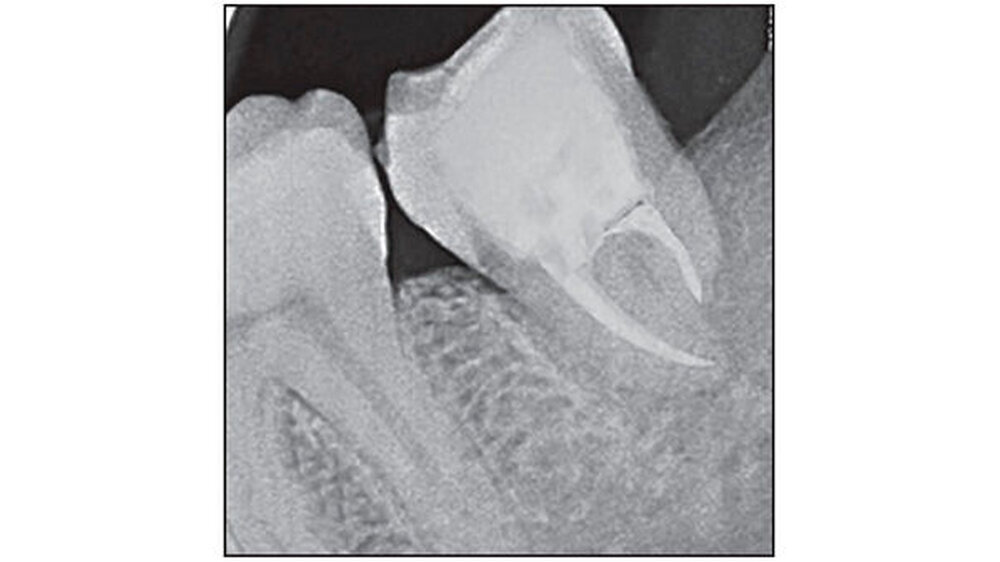

Bei einer Röntgenkontrolle nach vier Wochen präsentierte sich ein zufriedenstellender Heilungsverlauf am periapikalen Bereich. Der transplantierte Zahn wurde als stabil befunden. Der Wurzelkanal des Zahns 38 wurde mit Gutta Percha (Dentsply Maillefer, Ballaigues, Schweiz) gefüllt, danach folgte eine Versiegelung mit Sealapex (Kerr Corporation CA, USA). Die Wurzelkanalfüllung wurde per Röntgenbild überprüft (Abbildung 4). Die Patientin spülte anschließend drei- bis viermal täglich einen Monat lang mit warmer Kochsalzlösung.

Nach sechs, neun, 12 und 18 Monaten folgten weitere klinische und radiologische Kontrollen (Abbildungen 4 und 5). Bei jedem Besuch wurden der Mundhygienestatus, die Stabilität des Transplantats, die Sulkustiefe, Okklusion und die Wurzelresorption überprüft. Die vollständige Heilung war nach 18 Monaten erreicht.